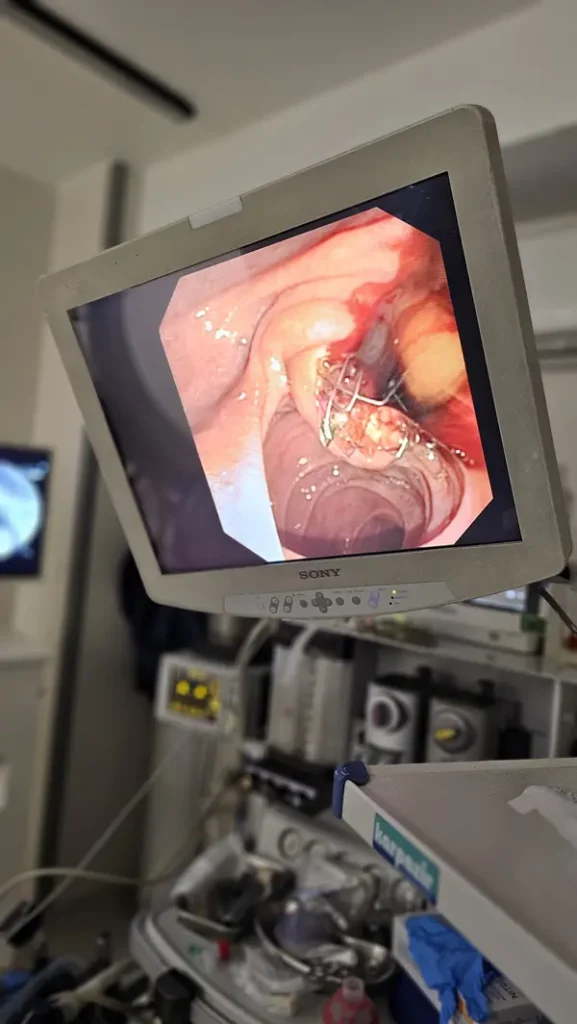

درباره ERCP بیشتر بدانیم

ERCP یک نوع تصویر برداری است که همانند آندوسکوپی از طریق دهان لوله ای وارد می شود. و از مجموعه صفراوی و پانکراست تصویربرداری انجام می شود.

در ادامه تصاویر و فیلم ERCP آقای ۶۶ ساله دارای سرطان سر پانکراس که غیر قابل عمل بود را مشاهده مینمایید.

ای آر سی پی در تشخیص سنگ های صفراوی، زخم ها، سرطان ها، تومورها و ضایعات احتمالی در لوزالعمده و پانکراست کاربرد دارد.

با استفاده از ERCP زردی و یرقان که در اثر انسداد مجاری صفراوی به وجود می آید را می توان درمان نمود.

همچنین بالن های خروجی سنگ های صفراوی با استفاده از ای ار سی پی انجام می شود.

مزیت ای آر سی پی در جلوگیری از جراحی های باز است.

نمونه هایی از عمل جراحی ERCP توسط دکتر رضادوست